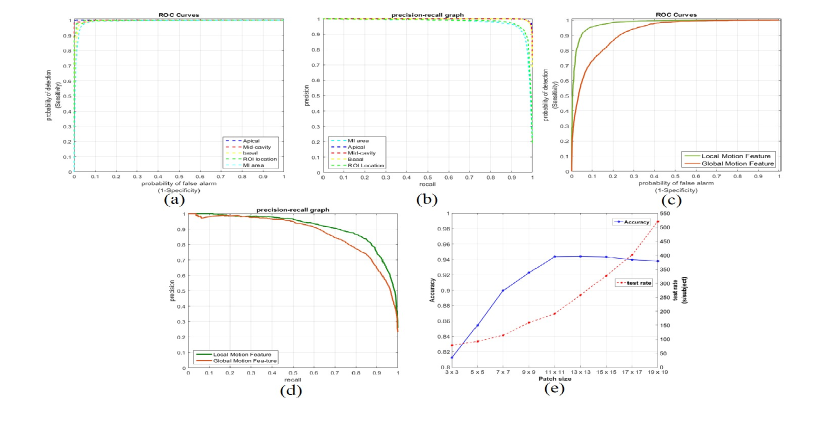

Automatic localization of the LV. The experiment’s result shows that OF-RNN can obtain good localization of the LV. We achieve an overall classification accuracy of 96.49%, with a sensitivity of 94.39% and a specificity of 98.67%, in locating the LV in the heart localization layers. We used an architecture similar to the Zeiler and Fergus model to pre-train the network. Using selective search s quality mode, we sweep over 2k proposals per image. Our results for the ROI localization bounding-box from 2.85k CMR images were compared to the ground truth marked by the expert cardiologist. The ROCs and PRs curves are shown in Fig. 3 (a-b).

MI area detection. Our approach can also accurately detect the MI area, as shown in Fig. 2. The overall pixel classification accuracy is 94.35%, with a sensitivity of 91.23% and a specificity of 98.42%. We used the softmax classifier by fine-tuning the motion statistical layers to assess each pixel (as normal/abnormal). We also compared our results to 16 regional myocardial segments (depicted as normal/abnormal) by following the American Heart Association standards. The accuracy performance for the apical slices was an average of 99.2%; for the mid-cavity slices, it was an average of 98.1%; and for the basal slices, an average of 97.9%. The ROCs and PRs of the motion statistical layers are shown in Fig. 3 (a-b).

Local and global motion statistical features. A combination of local and global motion statistical features has the potential to improve the results because the features influence one another through a shared representation. To evaluate the effect of motion features, we use local or global motion statistical features separately along with both motion features in our framework. Table 1 and Fig. 3 (c-d) show that the results that combine motion statistical features in our framework have better accuracy, sensitivity, and specificity in comparison to those that use only the local or global motion features, in another 10-fold cross-validation test.

Size of patch. We use an NN patch to extract the local motion features from the whole image sequence. Because the displacements of the LV wall between two consecutive images are small (approximately 1 or 2 pixels/frame), it is necessary to adjust the size of the patch to capture sufficient local motion information. Fig. 3 (e) shows the accuracy and computational time of our framework, using from 33 to 1717 patches in one 10-fold cross-validation test. We find that the 1111 patch size in our framework can obtain better accuracy in a reasonable amount of time.